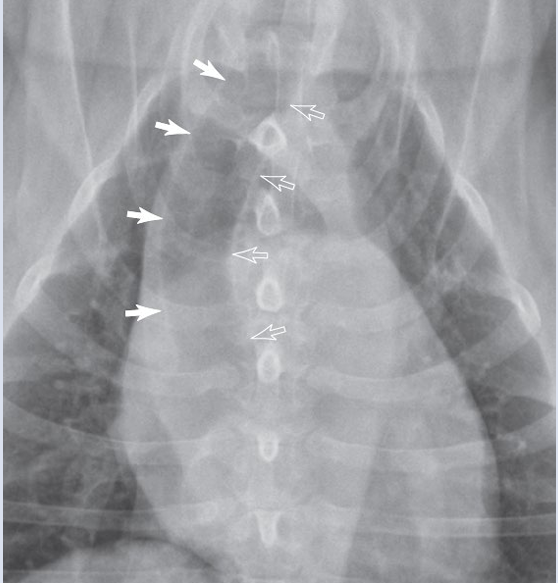

Interstitial pattern

aorta and vena cava is blurry

VD

Lymphomegaly